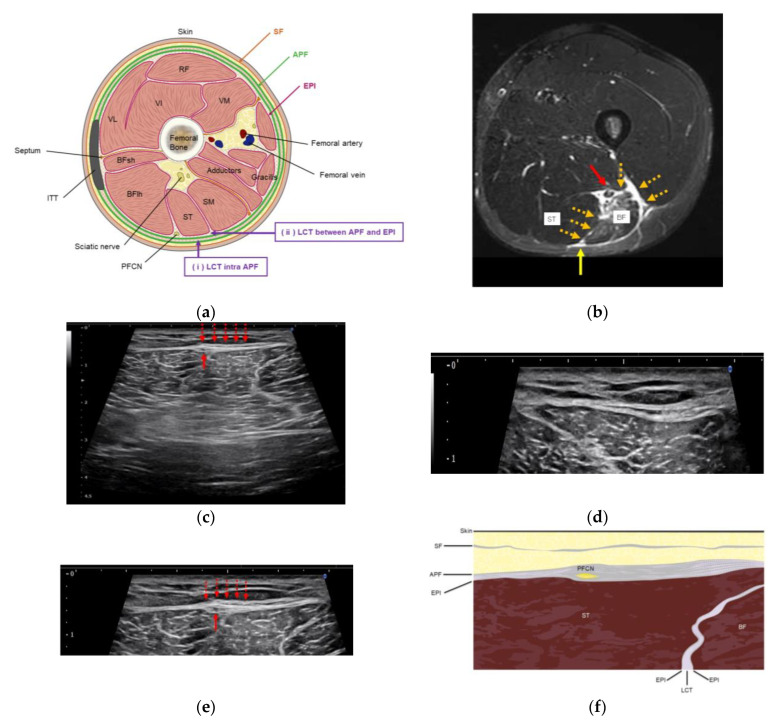

背景:腘绳肌腱损伤后的残余疼痛可能持续存在,尽管肌肉组织愈合并损害运动员寻求早期完全恢复。由于其原因尚不清楚,最近的注意力集中在筋膜功能障碍的作用和恢复筋膜活动的方法,即氢释放(HR),包括超声(US)引导下注射生理盐水。我们评估了HR治疗残余疼痛的临床疗效,并确定了其潜在的病理机制。方法:选取腘绳肌损伤后残余疼痛≥8周的7例患者,年龄17-49岁。所有患者均表现出局部压痛和超声显示腱膜筋膜(APF)周围的筋膜增厚。6.0 mL盐-利多卡因溶液(0.17%利多卡因)进行HR,靶向apf周围疏松结缔组织。采用数值评定量表(NRS)对HR前后疼痛进行评估。被动直腿抬高(SLR)用于评估松紧度。结果:术后NRS评分由10分降至0.86分,差异有统计学意义(p = 0.017)。4名患者需要一次HR会议;其中三个需要两到四个疗程。hr后,所有患者的松紧度均有改善。股后短轴超声显示压痛区APF筋膜增厚,包括股后皮神经(PFCN)。随访期间无不良事件及复发(平均6.6个月)。结论:HR靶向周围pfcn - apf可有效减轻腘绳肌损伤后的残余疼痛。这些发现支持了“神经周围筋膜疼痛”的概念,即持续性疼痛不是源于直接的神经损伤或经典的肌筋膜疼痛综合征,而是源于周围筋膜的功能障碍。

Background: Post-hamstring-injury residual pain may persist despite muscle-tissue healing and impairs athletes seeking early full recovery. Given their unclear cause, recent attention has focused on the role of fascial dysfunction and a method to restore fascial mobility, namely, hydrorelease (HR), involving the ultrasound (US)-guided injection of saline. We evaluated the clinical efficacy of HR for treating residual pain and ascertained the underlying pathological mechanisms. Methods: Seven patients (aged 17-49 years) with residual pain ≥8 weeks after hamstring injury were included. All exhibited localized tenderness and US findings of fascial thickening around the aponeurotic fascia (APF). HR with 6.0 mL saline-lidocaine solution (0.17% lidocaine) was performed and targeted the peri-APF loose connective tissues. Pain was evaluated using a numerical rating scale (NRS) before and after HR. Passive straight leg raise (SLR) was used to assess tightness. Results: Post-HR, the mean NRS score significantly decreased from 10 to 0.86 (p = 0.017). Four patients required a single HR session; three required two-four sessions. Post-HR, the tightness of all patients improved. Short-axis US of the posterior thigh revealed APF fascial thickening in the area of tenderness, including the posterior femoral cutaneous nerve (PFCN). No adverse events or recurrence occurred during the follow-up (mean: 6.6 months). Conclusions: HR targeting the peri-PFCN-APF effectively reduced residual pain following hamstring injury. These findings support the concept of "Perineural fascial pain"-a pathology wherein persistent pain originates not from direct nerve damage or classical myofascial pain syndrome but rather from the dysfunction of the surrounding fascia.